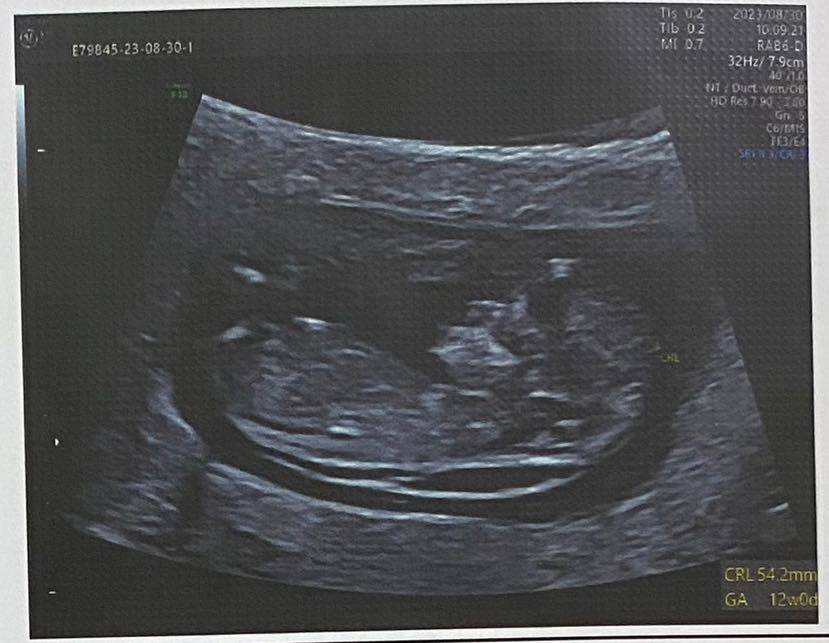

出院后,开启了两周一产检的日子

看着臭蛙崽子,一天天长大

长大

终于,昨天崽子做了四维了,放心了一半~